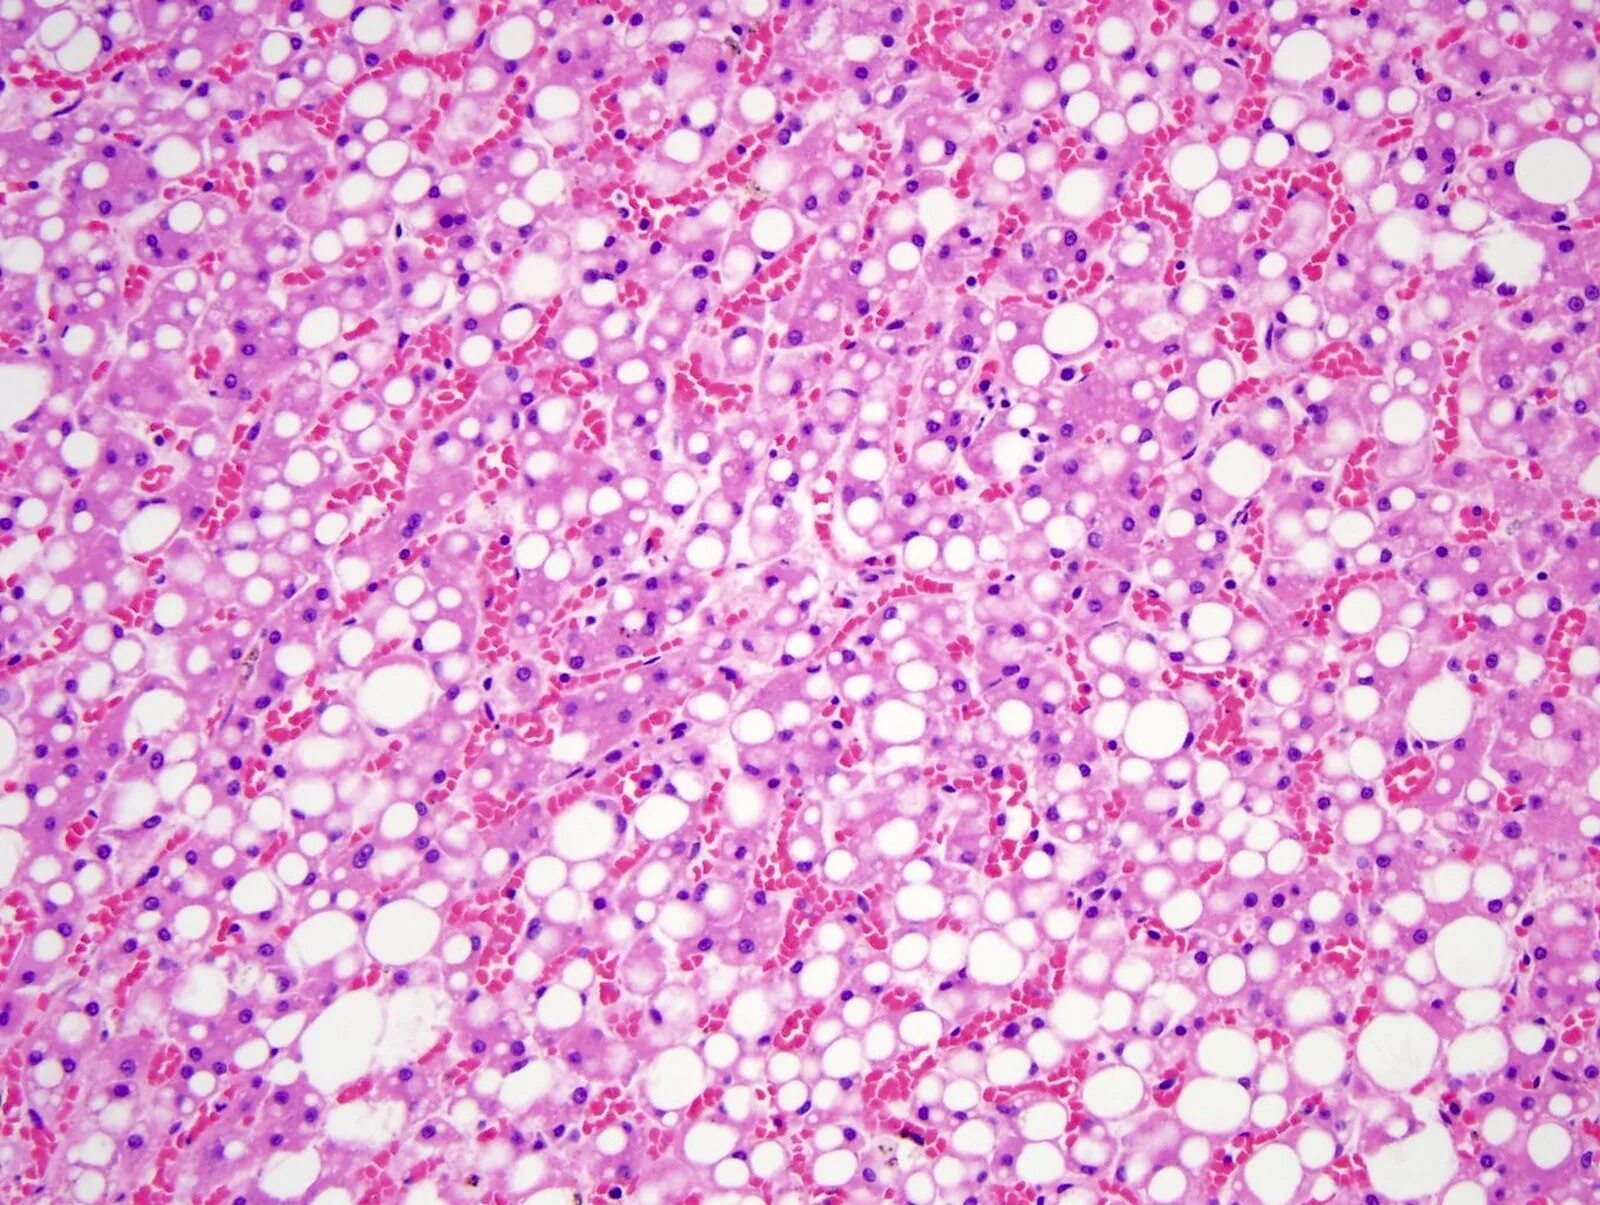

Молекулярная гистология